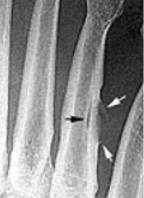

What do the arrows show? | Stress fracture |

Describe what has happened at the shaft of the 3rd met | Exuberant periosteal new bone production. May have resulted if a stress fracture was not treated and the patient continued weight bearing activities. |